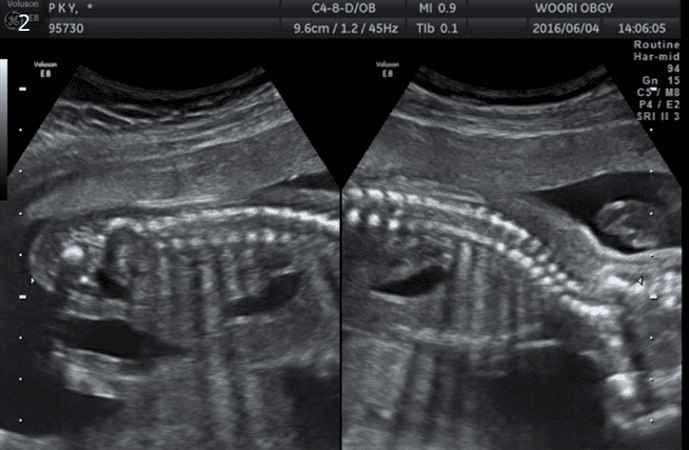

정밀초음파검사

태아의 기형을 진단하는 기본 초음파 검사이며 예약이 필요합니다. 임신 18-23주 사이에 태아의 장기를 세밀히 관찰하여 태아의 기형 유무를 확인하여, 출산 시 심한 기형으로 위급한 상황을 초래할 수 있는 태아(2-3%)를 진단하는 것이 목적입니다.